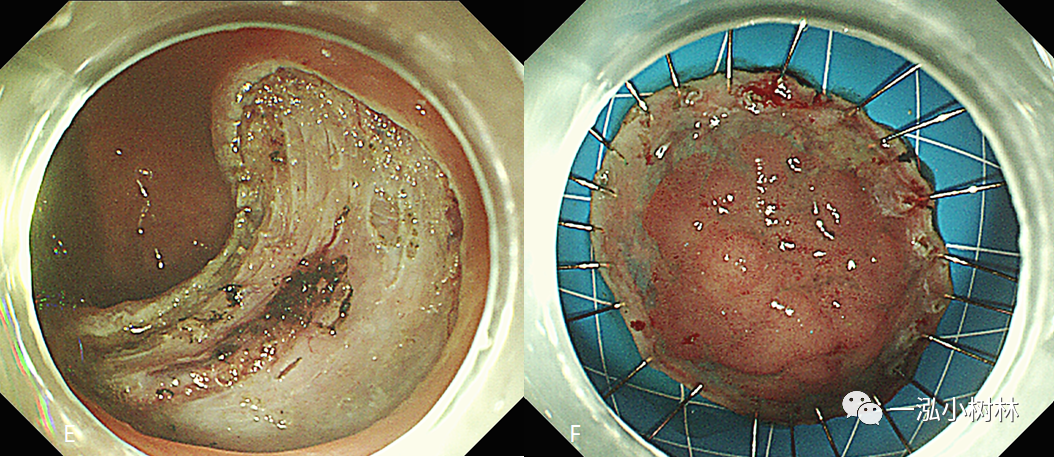

早期直肠癌

"直肠下段癌"老年男性患者,61岁,术前结肠镜检查诊断:直肠癌,距肛缘约

直肠癌